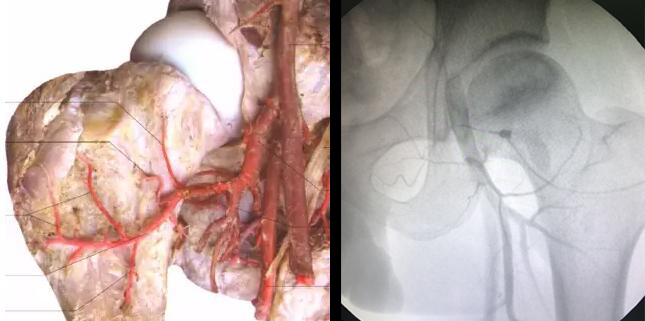

效果直击 “可视血堵融通术结合血液净化”综合治疗治疗后血管动态

临床证实:股骨头缺血性坏死之所以会坏死,首先是各种原因(激素、酗酒、外伤等)造成血液粘稠、以及形成大量的脂肪颗粒和血栓等,然后随着血液流淌,这些杂质不断沉积最终堵塞了股骨头的供血血管。而股骨头血供跟其他骨头不一样,它只有三根主要的动脉血管供应,如果血管堵塞了,骨细胞没有得到充足的营养供应,就会慢慢“饿”死,所以说只有疏通了这三根血管,同时建立起侧支循环,才能彻底解决了股骨头缺血性坏死的病根难题。

在此也提醒广大患者:“保髋”不仅仅是单一的融通血管,专业全面的检查是必要前提。股骨头三大血管中哪一根发生堵塞了?具体位置在哪里?堵塞程度如何?只有通过精准定位、系统检查,在全面了解了血管这些基本情况后,才能做到对症融通,直达病灶,为后续保髋方案的制定提供科学依据,一次科学的检查胜过十次盲目的治疗,在检查不清的情况下,切勿盲目融通!